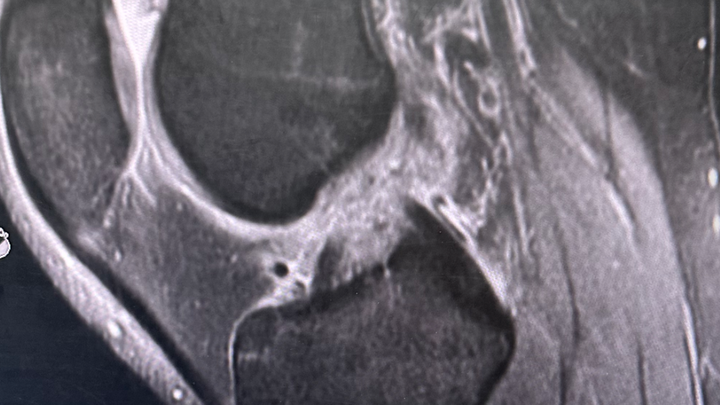

Hi, my name is Sasha and I’m currently facing a challenging medical situation. Three weeks ago I injured my knee and recent MRI scans revealed that I unfortunately have a complete tear of my ACL, damage to both sides of my meniscus, and an injury of my MCL.

The pathway to recovery is extremely extensive, including physical therapy both before and after an ACL reconstruction and meniscus repair surgery.